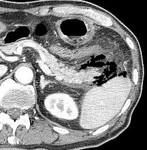

[画像診断]後腹膜気腫の原因について 2011-02-14